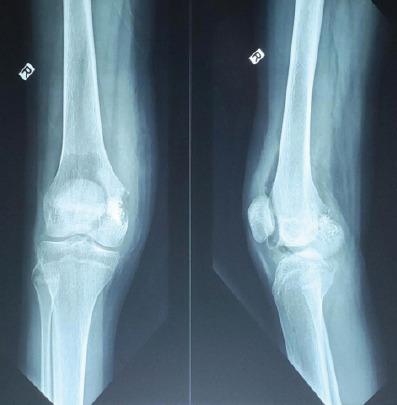

A 15-year-old female presented with progressive right knee pain of 6 months' duration, worsened by weight-bearing and minimally relieved by analgesics. Clinical examination revealed tenderness and immobile swelling in the region of the medial femoral condyle. Imaging showed characteristic "chicken-wire" calcification, and computed tomography-guided biopsy confirmed chondroblastoma. The patient underwent extended curettage, iliac crest bone grafting, and the use of synthetic bone substitutes. Post-operative rehabilitation showed a good recovery in range of motion and limb function, with no recurrence at follow-up.

一名15岁女性出现持续6个月的进行性右膝疼痛,负重时加重,使用镇痛药后稍有缓解。临床检查发现股骨内侧髁区域有压痛和固定性肿胀。影像学检查显示特征性的“筛孔状”钙化,计算机断层扫描引导下的活检证实为软骨母细胞瘤。患者接受了扩大刮除术、髂骨植骨及使用人工骨替代物。术后康复显示关节活动范围和肢体功能恢复良好,随访期间无复发。